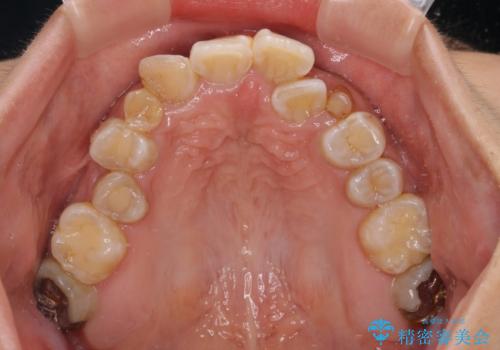

- 上下前歯のデコボコを気にして来院された患者様です。

上顎は両側の犬歯が骨内に埋伏しており、乳歯が残存している状態でした。

歯肉内に埋もれている場合には牽引することも可能ですが、両歯ともに骨内に完全に埋もれていたため、牽引することは不可能と判断しました。

口元の突出感があるわけではなく、叢生の程度もシビアではありませんでしたが、顎骨が小さく、左右ともに最後臼歯が歯肉に埋もれているため、下顎は左右第二小臼歯を抜歯することとしました。

上顎は左右ともに残存している乳歯を抜歯し、上下歯列を整えることとしました。